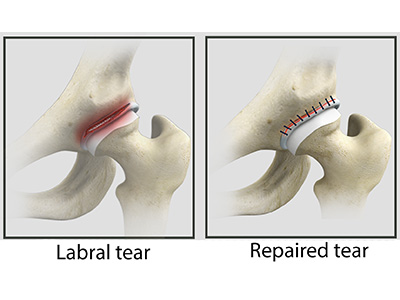

The head of the femur rotates and glides within the acetabulum. A fibrocartilagenous lining called the labrum is attached to the acetabulum and further increases the depth of the socket.

- Acetabular labrum: The labrum is a fibrous cartilage ring which lines the acetabular socket. It deepens the cavity, increasing the stability and strength of the hip joint.

Hip Ligament Injuries Hip Labral Tear

Hip Labral Repair Hip Labral Reconstruction

Hip Labral Reconstruction Hip Preservation Surgery